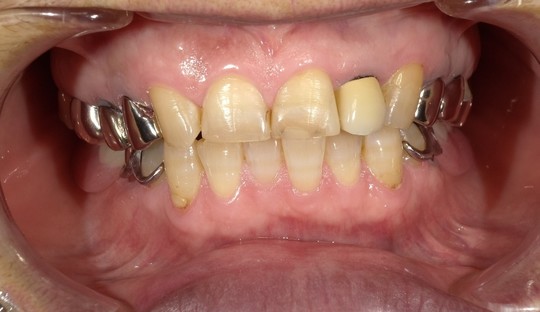

治療経験が豊富な院長が、技術のある歯科技工士とともに、お口にフィットしやすい入れ歯をお作りします。

前歯の審美修復

臼歯の審美修復